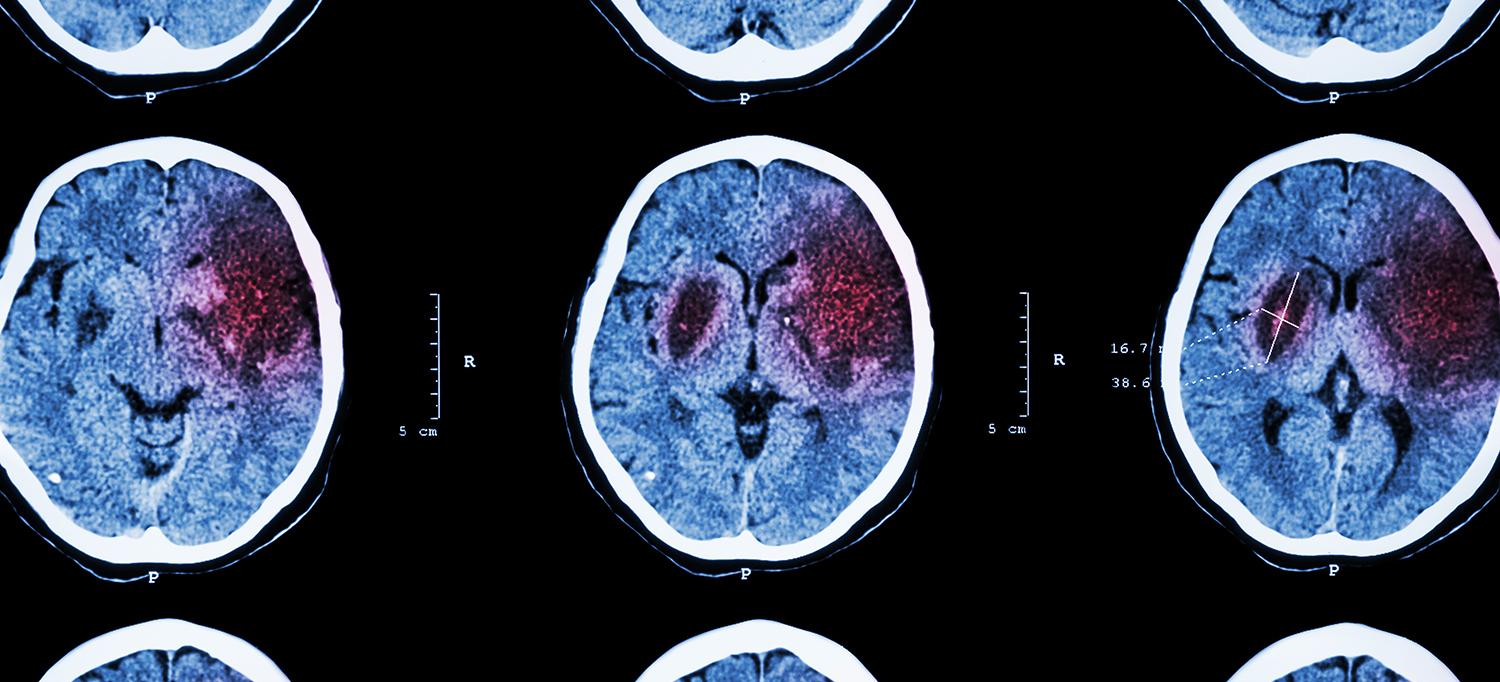

Photo: stockdevil/Getty